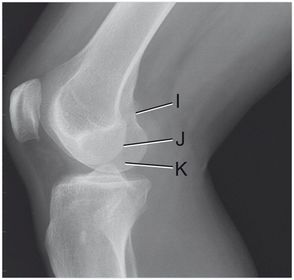

I. adductor tubercle J. lateral condyle K. medial condyle